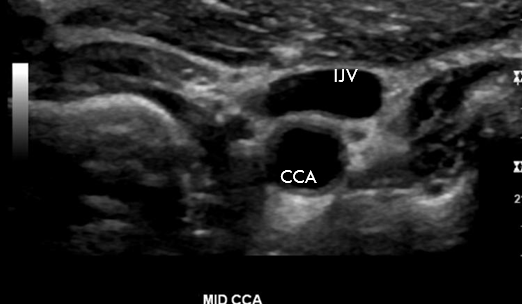

True or False: This image shows a Trans CCA sonographic appearance

True